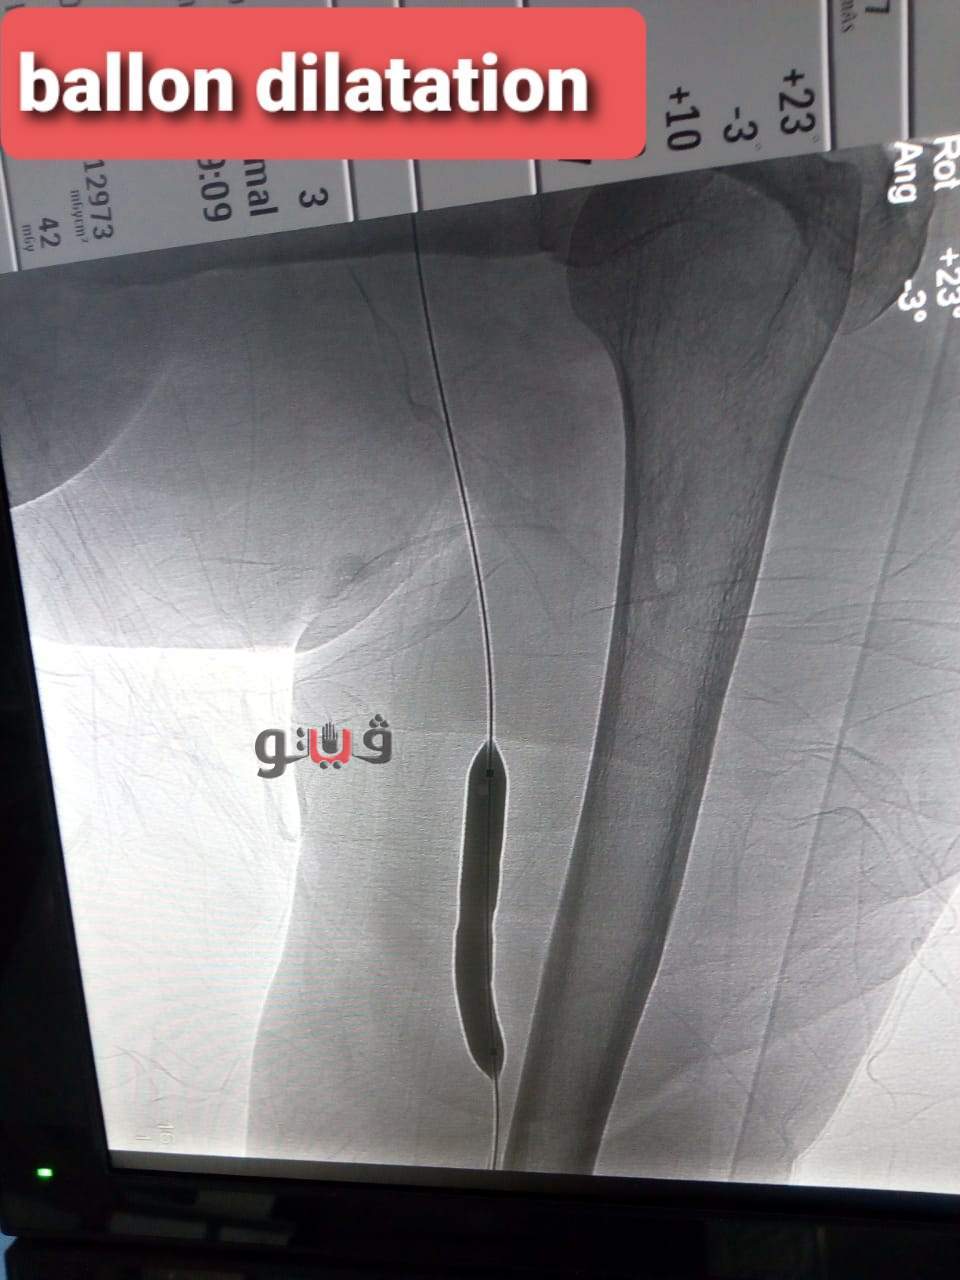

وتمكن الفريق الطبي من استقبال المريضة وعمل قسطرة تشخيصية وتصوير اوردة الذراع الايسر كما تم عمل تدخل علاجي بالقسطرة عن طريق توسيع الوصلة باستخدام البالونات عالية الضغط حيث تم توسيع الوصلة بنجاح .